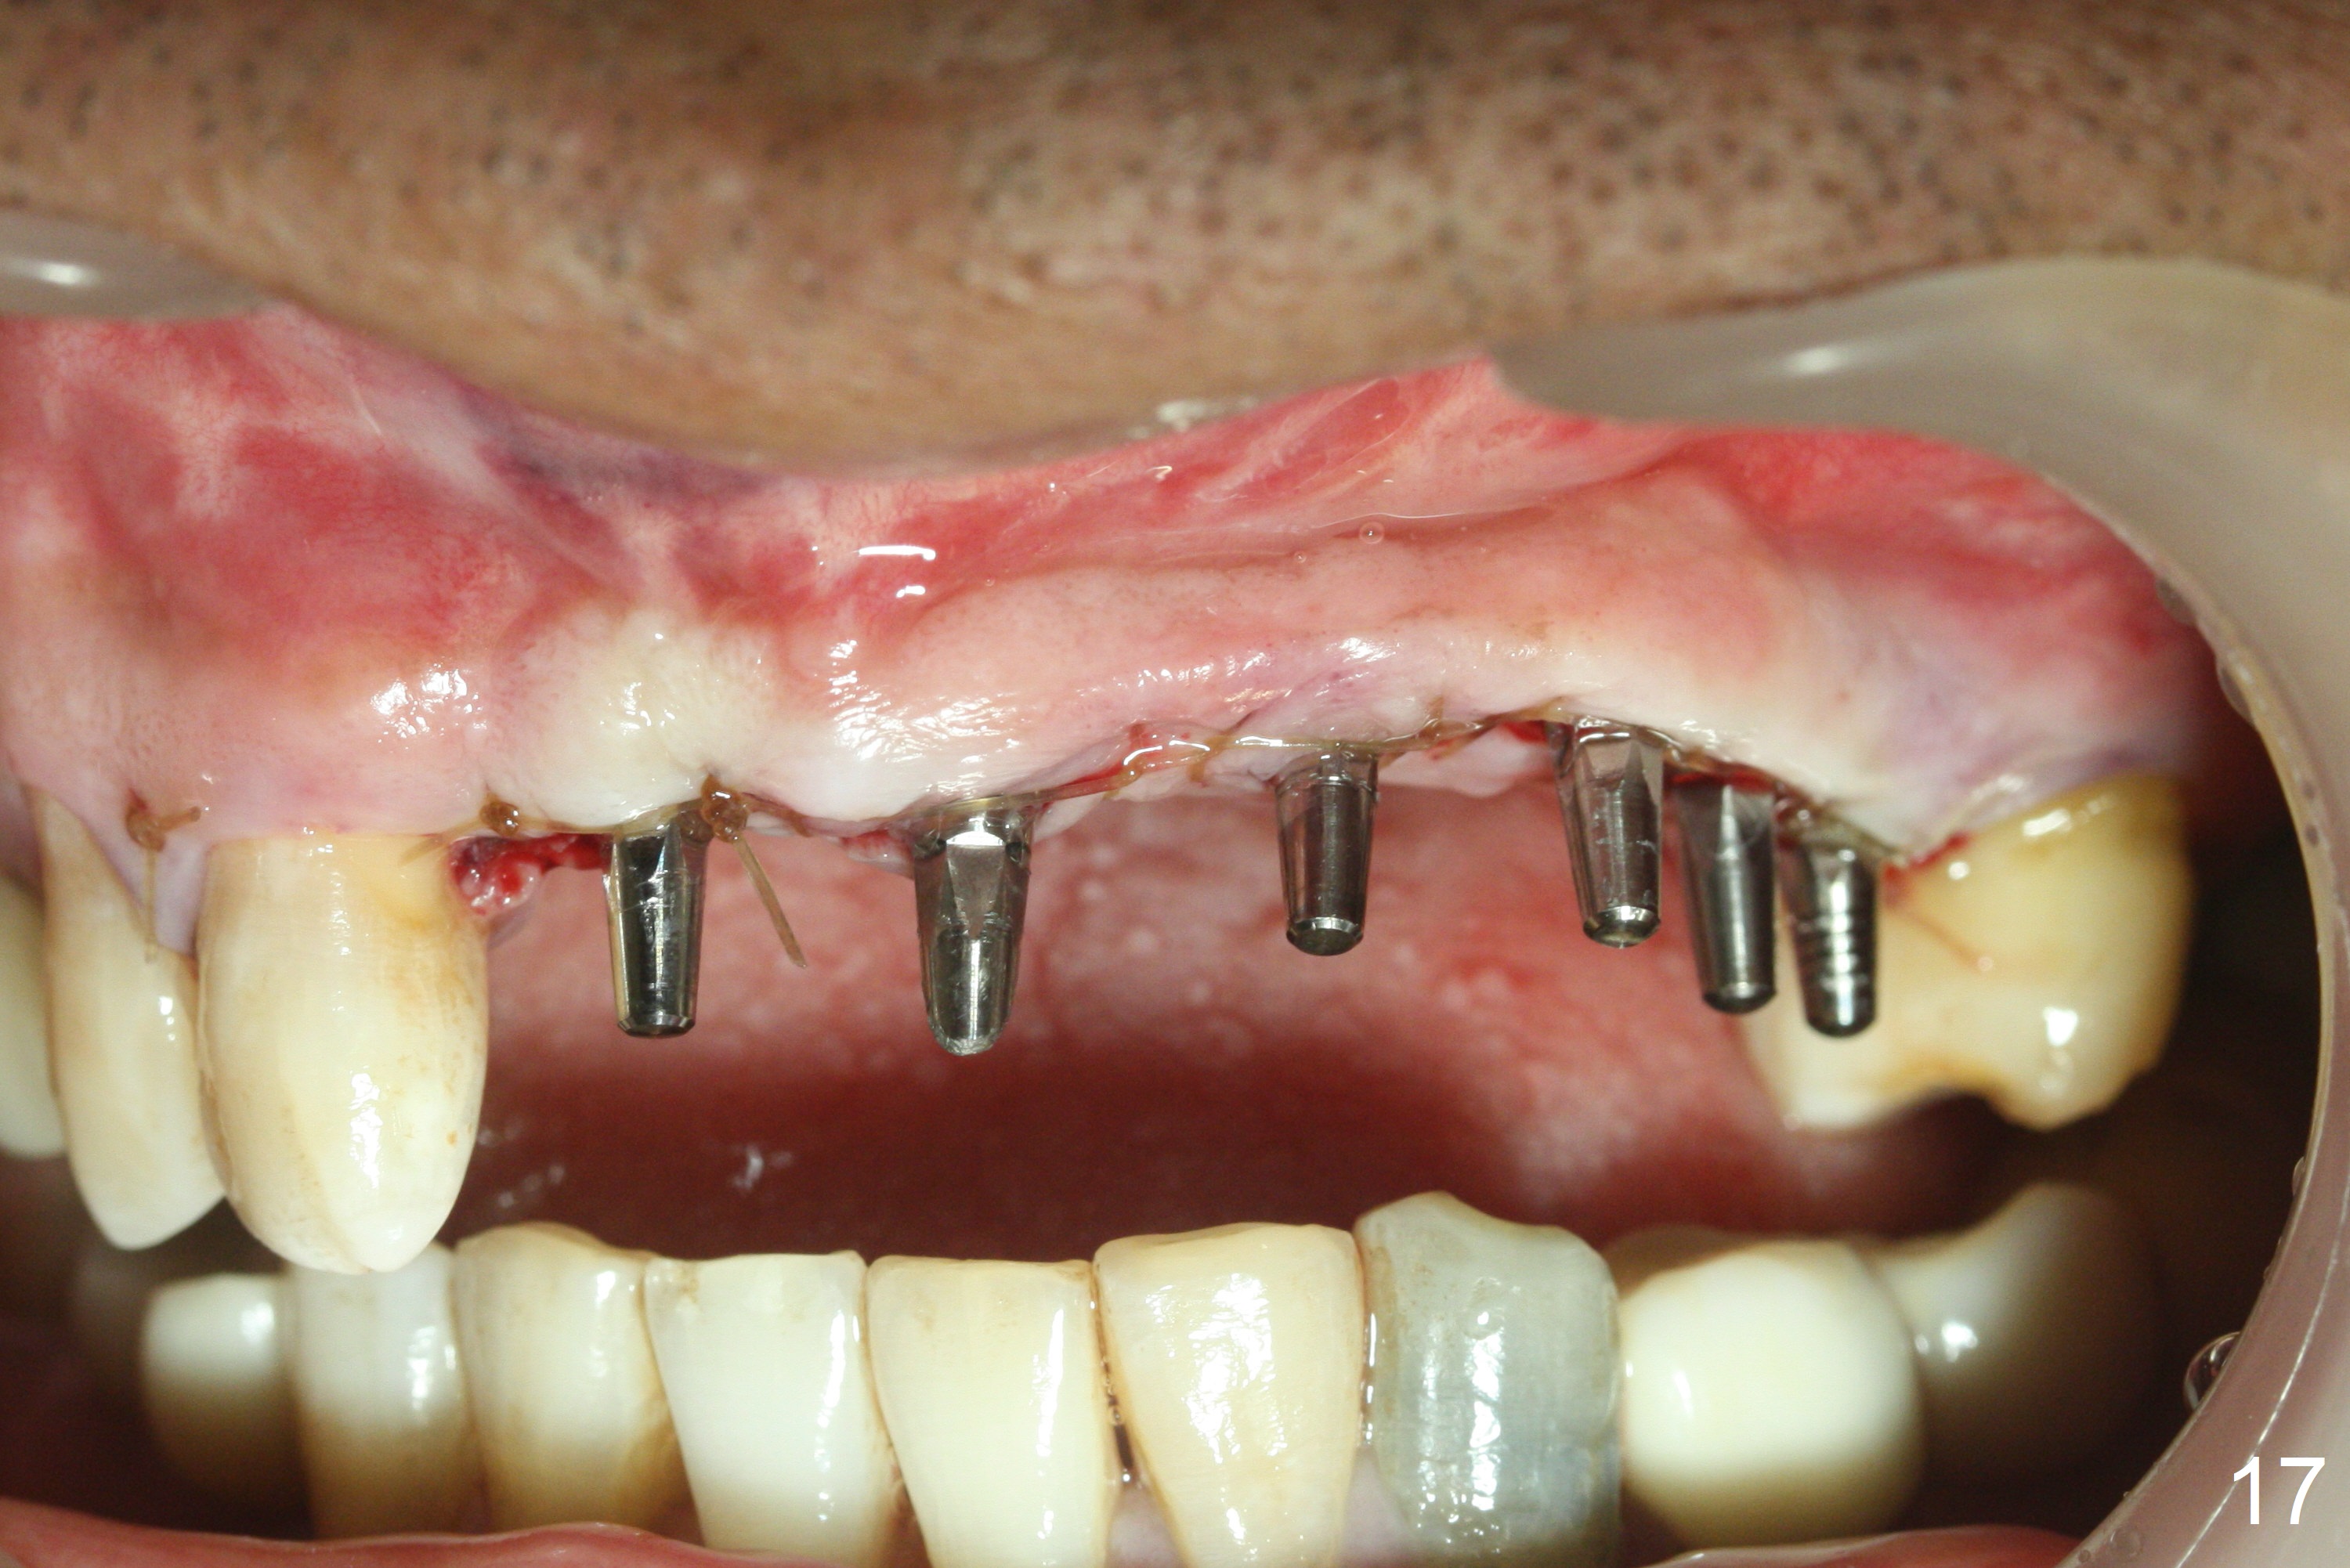

Following allograft placement around the implants (particularly palatally and in void due to change in osteotomy position) and PRF membrane buccopalatally, the ridge looks wider (Fig.17, 18) than preop (Fig.1). Note scar tissue in the upper labial vestibule (history of trauma). Continuous mattress suturing provides good wound closure.